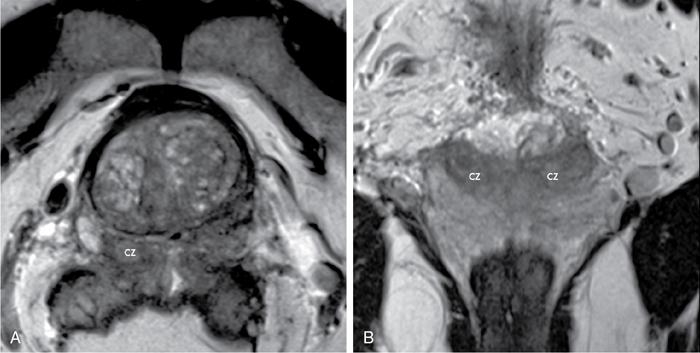

Karthik Ganesan, Disha Lokhandwala, Ujjwal Bhure, Jay Mehta Morphogenesis of the male genitourinary system is governed by the coherent interaction of three units, namely the Wolffian duct, urogenital sinus and foetal gonads. The Wolffian ducts are the embryonic precursors of the male internal genitalia, arising in the anterior intermediate mesoderm at 4 weeks of gestation. They elongate as a cord of cells that caudally extend to the urogenital sinus. Between 5 and 8 weeks of gestation, the urorectal septum divides the cloaca into a ventral compartment, which forms the urogenital sinus, and a dorsal compartment, which forms the rectum. The gonads form as epithelial thickenings on the ventromedial surface of the mesonephros and produce testosterone at 8 weeks of gestation, reaching a peak at 10–15 weeks. Under the effect of testosterone produced by the foetal testis, the prostate anlage forms at the tenth week of gestation. Precursor of the anlage begins with proliferation of solid epithelial buds from the epithelium of the urogenital septum into the adjoining mesenchyme in response to interaction of 5α-dihydrotestosterone with mesenchymal androgen receptors. As growth progresses, solid cords of epithelial cells are formed, growing into the mesenchyme in a specific three-dimensional arrangement (establishes the lobar divisions of the prostate gland). These solid cords develop a central lumen at birth and are lined by a layer of flat basal epithelium and a luminal layer of tall columnar secretory epithelium. Mesenchymal component forms the stroma, which has a large proportion of smooth muscle. Postnatally, the epithelial cords continue to arborize till puberty without any change in volume or glandular architecture. Although the foetal prostate has been described to have a histologically distinct peripheral zone (PZ) as early as 12 weeks of gestation, the mature zonal anatomy develops in concordance with the androgen surge at puberty. The most commonly utilized ultrasonographic technique for the evaluation of the prostate is via a suprapubic approach. The abdominal transducers used in this approach are relatively low frequency and while it offers the advantage of greater depth of penetration without intracavitary probe insertion; however, it does not depict the zonal anatomy and its chief application lies in volume estimation. Hence, transrectal ultrasonography (TRUS) completely outweighs the transabdominal approach in terms of depicting zonal anatomy, visualizing and localizing small lesions, demonstrating vascularity and performing biopsies. TRUS is performed using high frequency transducers (5–7.5 MHz) to optimize soft tissue resolution. An enema is administered 1 h prior to the examination to clear the field of insonation. Patient is positioned in left lateral decubitus, with knees bent toward the chest and ideally a digital rectal examination (DRE) is conducted prior to probe insertion. The transducer is first draped with a sterile barrier and lubricated, After insertion, the barrier is filled with 40–50 cc of water, making sure that no air enters. On completion, water is aspirated and the probe is withdrawn. The gland is initially scanned in the axial plane from the base to the apex, beginning at the level of the seminal vesicles, and the probe is gradually withdrawn to view the entire glandular parenchyma in axial sections up to its caudal aspect. This approach allows a cursory evaluation of glandular symmetry as both halves of the prostate can be evaluated simultaneously. Subsequently, sagittal views are acquired by rotating the probe across the transverse span of the gland, demonstrating the seminal vesicles, midline gland (visualizing both the apex and the base), with sequential scanning up to the contralateral margin of the gland. Sonographically, the prostatic capsule is seen as a smooth well-delineated, hyperechoic structure. With the newer ultrasound systems, the zonal anatomy can be delineated by TRUS; PZ appears echogenic relative to the central zone (CZ) and the transition zone (TZ), which are hypoechoic in juxtaposition (Fig. 11.12.1). Anterolaterally, the preprostatic venous plexuses are seen as anechoic tubular structures with intervening echogenic preprostatic fatty tissue. Glandular volume is estimated using an ellipsoid formula by obtaining the maximum anteroposterior, superoinferior and transverse dimensions and multiplying their product by π/6. Colour Doppler imaging is utilized to illustrate vascularity, as majority of the normal prostatic tissue (excluding the neurovascular bundles [NVBs] and pericapsular and periurethral regions) has symmetrical but sparse flow and an increased microvessel density raises the suspicion of prostatic carcinoma. However, the appearances of prostatic carcinoma can be variable on colour Doppler imaging, ranging from focal increase in vascularity around a nodule to an asymmetric increase in size and number of vessels on the affected side and conventional Doppler has found to elevate specificity by about 5%–10%. Additionally, Doppler imaging has also demonstrated some utility in distinguishing fibrotic tissue from local recurrence. However, vessels supplying cancerous tissue are of the order of 10–50 μm, which is well below the 1-mm resolution limit of conventional Doppler techniques. Contrast-enhanced colour Doppler imaging overcomes this limitation and facilitates imaging of microvessels, using intravenously administered microbubbles (less than 10 μm diameter) of an inert gas (sulphur hexafluoride) with a lipid or galactose shell, allowing quantification of blood flow in the cancerous microvessels. Additionally, these microbubbles act as vascular tracers and by monitoring the passage of a bolus injection through the tissue of interest, time–intensity curves are created. This permits the formulation of functional indices, including bolus arrival time, time to peak intensity, area under the curve and wash-in/wash-out curves. These indices can further extrapolate functional images, on a pixel-by-pixel basis, overlaid on grey-scale images. Quantitative methods to demonstrate perfusion are based on the destruction of microbubbles by high-power ultrasound pulses, and then observing the rate of microbubble replenishment in the field of interest to calculate flow rate. Halpern et al. utilized contrast-enhanced ultrasound and intermittent harmonic imaging with power Doppler, and exhibited an increment in sensitivity from 38% to 65% with a specificity of 80% in prostate cancer detection. Cadence contrast pulse sequencing (CPS) is a low-power multipulse imaging technique utilizing pulses with variable amplitudes and phases followed by a summation of the resulting echoes, permitting tissue suppression, allowing detection of even a small amount of contrast agents retained in the tissues. Real time elastosonography evaluates and quantifies tissue stiffness (Young’s modulus) by measuring strain under an applied stress (transducer compression) and maps areas of variable stiffness in colour-coded and grey-scale images simultaneously and shows potential in improving prostatic carcinoma detection. In a study comparing elastography and T2-weighted (T2-w) endorectal magnetic resonance imaging (MRI), similar sensitivity rates and negative predictive values (NPVs) were attained in the detection of prostatic carcinoma. Prostate gland is an inverted cone-shaped subperitoneal retropubic gland, with its base located rostrally and apex located caudally. The base is attached to the bladder neck and the apex sits on the urogenital diaphragm and abuts the medial surface of the levator ani muscles, namely the pubourethralis portion, which is separated from the inferolateral surfaces of the gland on either side by the prostatic venous plexus. Normal prostate gland measures approximately 4 × 3 × 3 cm, 15–20 g in weight, with a median volume of 11.5 mL (range, 1.6–20.6) in patients between 21 and 25 years and a median volume of 39.6 mL (range, 13–169.8) in patients between 38 and 83 years. The first comprehensive publication describing the anatomical subdivision of the prostate gland was in 1912 by Lowsley, based entirely on the embryonic glandular morphology at a series of gestational age groups. The budding prostatic ducts were seen to proliferate in five distinct clusters from the primitive urogenital sinus, which formed the basis of its lobar subdivision. It was divided into a ventral lobe (anterior to the urethra), two lateral lobes (lateral to the ejaculatory ducts), a posterior lobe (between the ejaculatory ducts) and a middle lobe (above the ejaculatory ducts). This classification had several shortcomings, the foremost being inclusion of only the embryonic prostate during its conception. Frank highlighted these aspects in 1953 and stated that no definite lobar boundaries exist in the adult prostate and further criticized the exclusion of periurethral glands (inner gland), identifying them as the sole site of origin of benign prostatic hyperplasia (BPH). The chief drawback of all research prior to 1968 was the lack of a concrete histological basis to support the seemingly arbitrary subdivision. McNeal was the first to ascertain histological heterogeneity within the glandular tissue and used it as the basis of his well-acclaimed prostatic zonal classification. The zonal anatomy of the prostate gland conceived by McNeal divided the gland into four distinct zones, namely the TZ, PZ, anterior fibromuscular zone (AFMZ) and the CZ (Fig. 11.12.2). McNeal used the plane of the distal urethra to describe the zonal relationships and divide the gland broadly into three parts, namely the base, midgland and the apex (Fig. 11.12.3). The improved understanding of the prostate anatomy coincided with the development of MRI in the late 1980s, which could depict the zonal anatomy, unlike ultrasonography (USG) or computed tomography (CT). Patterns of ductal growth and radiation from the prostatic urethra form the basis of the zonal anatomy of the gland. Ducts arising from the proximal urethral segment grow towards the urinary bladder. Tiny ducts which are confined by the preprostatic sphincter form the small periurethral gland, whereas ducts which develop distal to the lower border of the preprostatic sphincter extend laterally and then anteromedially to form the TZ. Ducts arising from the verumontanum in the vicinity of the ejaculatory duct orifices and are directed towards the base along the course of the ejaculatory ducts form the CZ, whereas ducts which arise from the lateral recess of the posterior urethral wall of the verumontanum and distal urethra radiate laterally to form the PZ and rostrally posterior to the CZ at the base of the gland. PZ is the dominant glandular component of the prostate gland comprising approximately 70% of the glandular tissue. On T2-w images, the normal PZ has a high T2 signal intensity (SI), owing to the abundant ductal and acinar elements with sparsely interwoven smooth muscle, and can broadly divided into three sections as per the sector map in Prostate Imaging Reporting and Data System Version 2.1 (PI-RADS v2.1), namely posterior medial, posterior lateral and anterior sections (Fig. 11.12.4). At the apex, the anterior sections have a horn-like morphology, curving anteromedially, to nearly encircle the urethra and abut the AFMZ. At the midgland level, the PZ comprises the posterior, both lateral and the anterolateral parts of the gland. At the base, the PZ is located posterior and superior to the CZ and TZ. CZ is an ovoid-shaped structure at the base of the gland, comprising approximately 25% of the glandular tissue, with its apex located at the verumontanum, surrounding the ejaculatory ducts. Beyond age 35, volume of the CZ starts to gradually diminish, as well as the CZ is compressed by the enlarged TZ. In the initial MR studies of prostate, the CZ could not be easily delineated from the TZ. Vargas et al. demonstrated in a population with a mean age of 60 years undergoing MR for prostate cancer assessment, the CZ was visible in 81%–84% of patients. Hansford et al. identified the CZ in 92%–93% of patients on T2-w images and 78%–88% of patients on apparent diffusion coefficient (ADC) maps. Histologically, substantial differences exist between the CZ and PZ, which reflect in the differential appearance on T2-w imaging. These differences are probably attributable to the differential origin, as the CZ is derived from the Wolffian duct, and the PZ and TZ are derived from the urogenital sinus. In the CZ, the acini appear larger and more irregular, with numerous epithelial covered ridges or septa project from the walls of the acini into the lumen, forming a characteristic Roman bridge architecture and intraglandular lacuna, with a prominent basal layer, crowded epithelial cells with granular eosinophilic cytoplasm, decreased luminal fluid and compact stroma. PI-RADS v2 has discouraged the use of the term central gland, as it is not reflective of zonal anatomy or reported on pathologic specimens. CZ demonstrates homogeneously low signal on the T2-w images and ADC maps and can, therefore, mimic prostate cancers. CZ is best identified on the coronal plane T2-w images paralleling the plane of the distal urethra, and appears as a symmetric paramedic paired structures surrounding the ejaculatory ducts from the base of the gland to the verumontanum (Fig. 11.12.5). TZ comprises approximately 5% of the glandular tissue of the prostate. On T2-w images, the TZ normally appears as a homogeneously hypointense structure surrounding the proximal urethra at the base and the midgland level; however, it can also demonstrate inconsistent SI, depending on the relative proportion of glandular and stromal elements (Fig. 11.12.6). Glandular hyperplasia produces higher SI (dominance of acinar elements and secretions), while stromal hyperplasia exhibits lower SI (dominance of muscular and fibrous elements). The TZ is easily demarcated from the PZ by a thick homogeneously low T2 signal surgical capsule, which becomes pronounced in BPH. With increasing age, the TZ demonstrates variegated signal on the T2-w images and ADC maps, due to differential growth of the stromal and glandular elements. AFMZ is a nonglandular muscular tissue that drapes the anterior surface of the gland, superiorly blending into the smooth muscles of the bladder neck and inferiorly extending to the prostatic urethra at the glandular apex. AFMZ is comprised of smooth muscles, which blends with the smooth muscle fibres surrounding the urethra, and rostrally merges with the bladder neck and preprostatic sphincter. High smooth muscle content of the AFMZ is responsible for the MR signature, where in it appears markedly hypointense on the T2-w images and ADC maps, and hypoenhances on the multiphase contrast series (Fig. 11.12.7). With the advancing age, temporal reduction in the size of the AFMZ is noted due to the compressive effects of the BPH. Capsule surrounds the prostate gland, anteriorly merging with the AFMZ anteriorly. Two discrete defects are identified in the prostate capsule, at the base of gland where the ejaculatory ducts enter the prostate and at the apex where in the stroma blends with the sphincter. The capsule is perforated along the anterolateral aspect by multiple vessels and nerves. The capsule appears as a thin dark rim surrounding the gland on the T2-w images and may reveal delayed enhancement on the postcontrast images (Fig. 11.12.8). Primary goal of radical prostatectomy (RP) is to achieve oncologic efficacy, both in terms of short-term and long-term clinical outcomes. However, as the majority of prostate cancers have an indolent clinical course, preservation of function in terms of continence and potency is equally important, and the key to this is a keen understanding of the fascial anatomy and neuroanatomy of the prostate gland. Fascial anatomy of the prostate gland is anatomically complex and poorly understood, and a thorough understanding of the interfacial planes is crucial to avoid mechanical or thermal injury to the NVBs. Periprostatic fascia comprises of a condensation of layers of connective tissue that encapsulate the gland and suspend it from anterior pelvic wall via puboprostatic ligaments. Laterally, the visceral and parietal endopelvic fascial layers fuse to form the fascial tendinous arch. Periprostatic fascia covers the prostate gland and capsule, comprises of two fascial layers, including an inner layer (prostatic fascia) and an outer layer (levator ani fascia), with thin interfascial planes separating these fascia from one another and the prostate capsule. Posteriorly, a continuous fascial layer known as Denonvilliers’ fascia covers the prostate and seminal vesicles. Distribution of periprostatic nerves is highly variable, with growing evidence of nerves both along the dorsolateral and ventrolateral surfaces of the prostate gland. Most of the periprostatic nerves are found posterolaterally; however, a significant portion of the nerves are located ventrally as seen by Eichelberg et al. (21.5%–28.5%) and Lee et al. (19.9%–22.8%). Although anatomic studies have confirmed the presence of ventrolateral periprostatic nerves, the exact clinical importance and functionality of these nerve fibres has not been proven. The cavernous nerves are situated posterolaterally and are the basis of nerve-sparing RP procedure proposed by Walsh and Donker. Unlike the initial theory of Walsh and Donker, few papers have proposed that the nerves are diffusely scattered along the surface of the gland in the form of a curtain or spray-like arrangement without clear bundle formation. Kourambas et al. assessed the precise relationship of the NVBs and cavernous nerves to Denonvilliers’ fascia and proposed that the nerves were not restricted posterolaterally, but were rather diffusely scattered within the fascia extending up to the midline (Lunacek et al., Takenaka et al.). On the basis of more diffuse arrangement of the periprostatic nerves, surgical techniques have been modified, resulting in a more anterior dissection called the ‘curtain dissection technique’ or alternatively a ‘superveil’ technique to preserve the NVBs within the lateral prostatic fascia. The NVB lies within areolar connective tissue surrounding the gland, which separates the capsule from the periprostatic fascia and provides a plane of dissection during nerve-sparing prostatectomy. Prostate gland is supplied and drained by periprostatic vessels, which also supply and drain the penis. Arterial supply of the gland is highly variable and is typically from branches of the internal pudendal artery, which course inferior to the gland prior to supplying the penile cavernosal tissue. Off late, these vessels have gained prominence in radiation-induced erectile dysfunction (ED) (potential vasculopathy), which have led to the development of newer vessel-sparing radiotherapy techniques. Further, with the advent of prostate arterial embolization in benign prostatic hypertrophy (BPH), the vascular supply of the gland is becoming increasingly vital to understand. Gland drains into the obturator, internal iliac, external iliac, common iliac and presacral lymph nodes. Dorsal venous complex is identified immediately ventral to the gland and also drains the penis. Periprostatic nodes are uncommon, are usually discovered near the base of the gland, and are only occasionally seen on MRI. Urethra is the principal anatomic reference point in the prostate gland. Urethra can be divided into a proximal segment and a distal segment, the point of differentiation being located at the verumontanum wherein the urethra makes an approximately 35-degree angulation. The angulation is highly variable and is further affected by the growth of the TZ. On MRI, the distal segment is more conspicuous vis-à-vis the proximal segment and appears a hyperintense core surrounded by a low signal rim on T2-w images. Preprostatic sphincter encases the proximal urethra from the base of the gland to the base of the verumontanum and merges with the AFMZ anteriorly. Verumontanum appears hyperintense on the T2-w images, lies within the distal urethral segment, beyond which the distal urethral segment is partially encircled by striated muscles which blend with the external sphincter beyond the apex of the gland. External sphincter is located distal to the apex is incomplete posteriorly and is anchored into the PZ and surrounds the membranous urethra. Damage to the external sphincter during RP or transurethral resection of the prostate (TURP) may lead to urinary incontinence. Seminal vesicles are paired structures identified posterosuperior to the base of the prostate gland, which appear as convoluted fluid-filled structures. Due to the high fluid content within the normal seminal vesicles, these structures appear as paired structures with intermediate signal walls surrounding a hyperintense core on T2-w images (Fig. 11.12.9). Vas deferens are paired structures located rostral to the base of the gland and anteromedial to the seminal vesicles and appear as cord-like structures with variable signal on the T2-w images. Duct of the seminal vesicle and vas deferens unite in the posterior aspect of the base of the gland to form the ejaculatory duct, which courses caudally to the verumontanum along the plane of the distal urethra, and drain into the orifices in the midconvexity of the verumontanum. Prostate-specific antigen (PSA) is a serine protease, secreted by epithelial cells of the prostate gland and has been found in normal, benign and malignant prostatic tissues. Traces of PSA have also been isolated from endometrial tissue, breast tissue, adrenal neoplasms and renal cell carcinomas; however, for all clinical purposes, PSA is considered as an organ-specific biomarker. Papsidero first demonstrated and quantified serum PSA, which steered the epoch of prostate cancer screening and early detection of prostatic carcinoma. Subsequent studies showed that PSA screening often led to overdiagnosis of low-grade prostate cancers, with no survival difference between the PSA screened and nonscreened groups. Additionally, PSA levels were found to be elevated in a spectrum of prostatic pathologies apart from carcinoma, including prostatitis and benign hyperplasia. The likelihood of overdiagnosis coupled with the lack of specificity set grounds for the longstanding PSA controversy. Did the benefits of screening outweigh the risks of overtreatment? To elevate the specificity of serum PSA testing, a plethora of indices were devised, including free PSA and total PSA, free-to-total PSA (f/t PSA) ratio, age-specific PSA, PSA velocity (PSA-V) and PSA density (PSAD). Serum PSA exists in three forms; the major form (approximately 75%) is bound to alpha-1-antichymotrypsin, followed by free PSA (constituting 5%–50% of serum PSA). The third form (PSA bound to alpha-2-macroglobulin) is not clinically relevant and cannot be detected by any commercial test. A study by Stenman et al. established that a higher proportion of bound PSA and hence a lower ratio of f/t PSA is associated with prostate cancer. Conversely, free PSA can be utilized during follow-up for men with an initial negative biopsy result, wherein declining free PSA with a persistently elevated total PSA would raise suspicion of a neoplastic aetiology. As per the ACS guidelines (Table 11.12.1) for early detection of prostate cancer, men with a 10-year life expectancy or higher should have the opportunity to make an informed (regarding benefits, risks and uncertainties associated with PSA screening) decision for serum PSA testing, with or without DRE. For those who choose to undergo PSA screening, subsequent screening interval is determined on the basis of baseline PSA value. For values below 2.5 ng/mL, screening interval can be extended to 2 years and for PSA between 2.5 ng/mL and 4 ng/mL, an individualized approach is adopted following risk assessment to recommend either further referral or screening on a yearly basis. A PSA level of 4 ng/mL or higher warrants referral for further evaluation or biopsy, for men at average risk for prostate cancer. Although age-specific PSA (Table 11.12.2) is not a component of the ACS guidelines, it is considered as a beneficial parameter in determining the need for biopsy. As there is an expected rise in PSA values with age, setting a lower cut-off value for younger men would increase the sensitivity of detecting organ confined cancers and a higher value in older men would increase specificity. aThere is no proven rationale for using a single PSA-V threshold value. PSA screening guidelines for treated localized prostate cancers are variable and the definition of biochemical (PSA) recurrence remains debatable. Due to this inconsistency, the Prostate Cancer Guidelines Update Panel recommended a standard definition for biochemical recurrence (BCR) after RP and set a cut-off serum PSA (acquired between 6 weeks and 3 months of surgery) of 0.2 ng/mL or greater, along with a second confirmatory PSA. While there is a significant fall in PSA values after RP and a single raised PSA is sufficient to raise suspicion of recurrence, postradiotherapy recurrence requires a rising trend rather than a single cut-off value. The ASTRO Consensus Panel defined postradiotherapy prostate cancer recurrence as three consecutive raises in PSA values after a baseline has been reached. A hiatus in this definition was that no specific time interval between consecutive increases in PSA was determined. In addition to its utility as a screening tool, PSA is also a good prognosticator when used in conjunction with biopsy Gleason score and clinical T-stage, and several pretreatment prostate cancer risk stratification systems are based on these indices. D’Amico et al. proposed a three-group risk stratification system in 1998, which categorized nonmetastatic (M0) carcinomas as low risk, intermediate risk and high risk. Low-risk prostate cancer was defined as 1992 AJCC T1/T2a, PSA ≤10 ng/mL and Gleason score ≤6. Intermediate-risk prostate cancer was defined as 1992 AJCC T2b, and/or PSA 10–20 ng/mL and/or Gleason 7 disease. High-risk disease included any one of the following: 1992 AJCC ≥T2c, PSA >20 ng/mL or Gleason 8–10 disease. In 2001, the GUROC published the results of a consensus meeting which categorized the groups as follows: low risk – 1997 AJCC T1–T2a, PSA ≤10 ng/mL and Gleason ≤6; intermediate risk – 1997 AJCC T1–T2, PSA ≤20 ng/mL and Gleason ≤7 not otherwise low risk and high risk – 1997 AJCC T3–T4 or PSA >20 ng/mL or Gleason 8–10. In due course, newer classification systems have been developed (Table 11.12.3), including the National Comprehensive Cancer Network (NCCN, USA), National Institute for Health and Clinical Excellence (NICE, UK), European Society of Medical Oncology (ESMO), American Urological Association (AUA) and the European Association of Urology (EAU). The NCCN guidelines also incorporate very low-risk (T1c, and Gleason score ≤6, PSA ≤10 ng/mL, <3 positive biopsy cores each ≤50% involved and PSAD of <0.15 ng/mL/g) and very high-risk (T3b–T4) categories. AUA, American Urological Association; EAU, European Association of Urology; GUROC, Genitourinary Radiation Oncologists of Canada; NICE, National Institute for Health and Clinical Excellence; CAPSURE, Cancer of the Prostate Strategic Urologic Research Endeavour; NCCN, National Comprehensive Cancer Network; ESMO, European Association of Urology; T, T-stage; GS, Gleason score; PSA, prostate-specific antigen. Note: Use of the 1997 TNM staging system (T2a one lobe involvement, T2b two lobes involvement, no T2c category). PSA, DRE and TRUS form the diagnostic triad for prostatic carcinoma. It has been well established that manipulations of the prostate gland, including prostatic massage, cystoscopy and perineal biopsy cause a potential increase in serum PSA levels. This raised the question of TRUS affecting PSA levels and it was found to cause a very small rise in PSA only in patients with prostatitis. The effect of DRE on serum PSA levels is also controversial, while some studies found a transient increase in PSA, others found no significant rise in PSA levels after DRE. Therefore, it is advisable to obtain blood samples for PSA testing either prior to DRE and TRUS or after at least 7 days. PSA-V refers to the change in PSA over time using serial measurements. Ideally, at least three consecutive measurements over at least 18–24 months should be used. Carter et al. first defined PSA-V and found that a value of 0.75 ng/mL per year or greater was indicative of carcinoma with a high sensitivity and specificity. Consequently, several studies disproved a definite relationship between PSA-V and prostate cancer, stating that there was no rationale behind a single threshold value for PSA-V. Further, it was found that calculating PSA-V was arduous and while elevated PSA values on serial examinations should raise alarm, there was no added benefit of formally calculating PSA-V. As per NCCN guidelines, the PSA-V cut-off should be based on the initial PSA value with a PSA-V of 0.35 ng/mL/y, when the PSA is ≤2.5 ng/mL and 0.75 ng/mL/y, when the PSA is 4–10 ng/mL PSAD was developed in order to correlate prostate volume and PSA values. The basis of PSAD was that cancer cells produce more PSA per unit volume than normal cells. It is calculated as PSA value divided by the prostate volume as determined by TRUS. This reliance on TRUS leads to interobserver variability and hence PSAD values would differ with the performing sonologist. The chief utility of PSAD is in the diagnostic grey zone of PSA values between 4 and 10 ng/mL and the most commonly used cut-off value is 0.15 ng/mL/cc. However, more recent studies have shown that a value of 0.08 ng/mL/cc has an NPV of 95% in predicting prostate cancer. Additionally, PSAD in conjunction with MRI (PI-RADS score) has proved to be a reliable prognosticator for Gleason score upgrading. The most significant application being avoiding unnecessary biopsies as PI-RADS scores of 1–3 along with PSAD values <0.15 ng/mL/cc showed no Gleason score upgrading on repeat biopsies. In summary, most guidelines recommend shared decision-making for screening of prostate cancer. Limited testing should be conducted in men with low PSA values and a lower life expectancy. The aim should be to overcome challenges posed by the inherent nonspecific nature of serum PSA and reduce superfluous testing, unwarranted biopsies and overdiagnosis. Reliance on parameters like PSA-V that do not have a proven scientific basis is avoidable. Whereas applications of PSA like PSAD along with MRI can greatly reduce patient burden by avoiding follow-up biopsies. Lastly, PSA has no role in assignment of a PI-RADS category, which is based on multiparametric MRI (mpMRI) findings alone. Several ‘novel biomarkers’ are now being developed which are more specific in detecting high-grade prostatic carcinomas. Other human kallikrein proteins have been identified, as prostate cancer biomarkers, of which, human kallikrein 2 (hK2) has shown a high specificity. While hK2 and PSA have an overlapping primary structure, malignant cells express hK2 to a higher degree than benign epithelial cells, particularly in aggressive cancers. Engrailed-2 (EN2) is an HOX gene family transcription factor seen exclusively in malignant prostate tissue, with a reported sensitivity and specificity of 66% and 88%, respectively. Annexin A3 is a calcium-binding protein measured in urine samples following prostatic massage, potentially reducing unnecessary biopsy in men with a PSA of 2–10 ng/mL. However, extensive prospective evaluation of these biomarkers is necessary to replace PSA testing in clinical practice. Positron emission tomography (PET)/CT has evolved over the last two decades to make a paradigm shift in the field of imaging, moving from morphological imaging to molecular level and completely changing the approach to how we view the disease. Though the main workhorse tracer in the field of PET/CT is 18-fluorine-fluorodeoxyglucose (18F-FDG), it has limitations with regard to prostate cancer, especially in indolent or well-differentiated ones. However, that void has been filled up by the new kid on the block and that is prostate-specific membrane antigen (PSMA)-based radiotracer. PSMA is a type II transmembrane protein with intracellular (19 amino acids), transmembrane (24 amino acids) and extracellular (707 amino acids) domains, which functions biochemically as a glutamate carboxypeptidase. After a ligand binds to PSMA, internalization occurs and it is either retained in lysosomal compartments or released into the cytoplasm. PSMA expression and localization in the normal human prostate is associated with cytoplasm and apical side of the epithelium surrounding prostatic ducts but not basal epithelium and neuroendocrine or stromal cells. Neoplastic transformation of prostate tissue results in the transfer of PSMA from the apical membrane to the luminal surface of the ducts. PSMA is an ideal target for molecular imaging of prostate cancer as its expression is significantly upregulated in prostatic carcinoma cells compared to benign prostatic tissue, in density (100 to 1000 times) as well as activity (8 to 10 times). PSMA expression increases with increase in Gleason score, stage and grade of tumour, with further increased expression with transition to androgen-independent/castration-resistant prostate cancer. PSMA-binding analogues, because of their high sensitivity and specificity, possess precise imaging characteristics required for critical decisions in the management of prostate cancer (PCa). The most commonly used PSMA radiotracer is 68Gallium-PSMA-11, followed by 18F-PSMA. The availability of 18F-labelled PSMA radiopharmaceutical has helped to advance the reach of PSMA PET imaging to wider locations owing to higher available amount of the radiotracer due to its production from a cyclotron, compared to 68Ga-PSMA which is eluted from individual in-house generator. Additional benefit is accrued with excellent image quality owing to optimized radiotracer doses, higher imaging statistics and favourable decay properties of 18F radioisotope. The normal physiological biodistribution of PSMA-based radiotracers is seen in lacrimal and salivary glands, liver, spleen, kidneys and intestine. Physiological activity is also seen in celiac and cervicothoracic ganglia. Unbound PSMA radiotracer is excreted by the kidneys into the urinary bladder. PSMA PET/CT has established roles of varying degrees in the imaging of different aspects of prostate cancer including primary diagnosis, staging, BCR after primary prostate cancer treatment (prostatectomy), identification and significance of oligometastasis, restaging and treatment response assessment and monitoring. PSMA PET/CT is useful at the stage of diagnosis in that subset of patients with tumour-negative biopsy samples, by contributing the useful molecular information to mpMRI, helping to precisely delineate suspicious lesions for targeted biopsies. In intermediate-risk to high-risk primary prostate cancer patients, PSMA-based imaging has shown improvement in detection of metastatic disease compared to the CT and mpMRI, which has led to reduced demand and dependence on additional cross-sectional imaging or bone scintigraphy. Furthermore, PSMA PET/CT has also established its clear advantage over conventional imaging in patients with biochemically recurrent prostate cancer with improved and increased detection of metastatic sites even at low serum PSA values. As it happens in cancer, biopsy is the standard of diagnosis and likewise in PCa, it is the multicore biopsy, which is the gold standard. However, because of its size, location, approach and sensitive and delicate nature, yield and accuracy can often be restricted, especially in inexperienced hands. The diagnostic yield of biopsy can go down as low as 40% and false negative (FN) rate can climb as high as 25%–30%. PSMA overexpression follows high-grade PCa cells and increases with Gleason score. In normal prostate tissue, PSMA to PSA ratio is about 1, which decreases in BPH, increases in primary PCa cells, further increases with intratumoural angiogenesis, higher in metastatic lesions than in primary PCa cells and further upregulated in castration-resistant situation. In a study by Litwin and Tan in 2017, the FN rate of multicore biopsy was around 21%–28% and about 15% of the cases were undergraded vis-à-vis final prostatectomy results. While the diagnostic accuracy of random multicore biopsy was around 76.3%, that of 68Ga-PSMA PET/CT was upward in the range of 85.5%. The role of PSMA PET/CT in the primary/initial diagnosis of prostate cancer is generally limited to clinically intermediate-risk to high-risk patients with negative biopsy or reluctance to biopsy or noncooperation or nonfeasibility and for confirmation and staging in clinically high-risk patients. In low-risk patients, metastatic spread is very unlikely and hence it is a relative indication at the time of initial diagnosis in low-risk patients. And, its role in screening is variable and debatable (Fig. 11.12.10). Staging is crucial as it has considerable influence on deciding further line of management and treatment choices, which includes RP, radiotherapy or palliative systemic treatment, deciding on the extent of the pelvic nodal dissection during surgery, planning the radiotherapy field and consideration of multimodal therapy. Accurate staging helps to make the most appropriate choice of treatment modality (Fig. 11.12.11). In a meta-analysis of five studies with histopathology as gold standard, which included 216 patients, the per-lesion sensitivity of 68Ga-PSMA PET/CT ranged from 33% to 92% (33% value being an outlier due to the retrospective analysis based only on the reports, in absence of the images) with higher specificity of 82%–100%. For T-staging, PSMA PET/CT showed a significantly higher tumour detection rate of 92% vis-à-vis 66% with MR alone. In regard with N-staging, the majority of metastatic nodes from prostate cancer are small subcentimetre-sized, less than 8 mm, which are overlooked, missed or inconclusive on morphological imaging (CT and MRI) (falling below size criteria for morphological imaging). Accurate N-staging is important because lymph node involvement is a critical prognostic factor in cancer management, and precise pelvic nodal clearance could be curative and could make a difference in treatment success and long-term outcome in prostate cancer (Fig. 11.12.12). Also, accurate prediction of pelvic nodal metastases may spare nodal dissection, shorten surgical time and in turn help to reduce undesirable complications. In one study from 2016 involving 130 patients with intermediate-risk to high-risk prostate cancer, the metastatic nodal detection rate by 68Ga-PSMA PET was around 66% compared to 44% with MRI. PSMA PET has shown superior predictive value for surgical response over Gleason score, pT stage and PSA (at the time of imaging). In a literature overview by Luiting et al. in 2019 involving 9 retrospective and 2 prospective studies, the specificity of PSMA PET/CT in detection of pelvic nodal metastases before initial treatment reached as high as 80%–100%. PSMA PET/CT increases the confidence level in the evaluation of nodal metastases and an NPV reaching up to 86%. With imaging becoming more precise and adding different modalities together, the question arises about the tiny nodes less than 5 mm size. In a study by van Leeuwen et al. in 2017, the mean size of missed lymph node metastases was 2.7 mm. In a recent study by Ferraro et al. in 2020, about the impact of PSMA PET staging on clinical decision-making in intermediate-risk to high-risk prostate cancer patients, PSMA PET provided new information in 36% of patients and this helped to change treatment decision in nearly 27% of patients, which means in every fourth patient they studied. PSMA PET in combination with CT or MRI can achieve complete and precise Tumor, Nodes and Metastases (TNM) staging including staging of local tumour, nodal assessment and bone and organ/visceral metastases, in one single imaging session, with improved accuracy and better outcome, and in turn leading to precise treatment planning, eventually superseding conventional imaging. Accurate localization of prostate cancer lesions in patients with BCR is a major challenge. Especially at low serum PSA values (as low as less than 0.5 ng/mL), the precise determination of localized disease and metastatic spread is of great importance for further disease management. Conventional imaging modalities including CT scan or bone scintigraphy have limited detection rate for metastatic disease at low serum PSA values in this setting of BCR. PSMA PET/CT imaging plays a very valuable role in the evaluation of BCR (Fig. 11.12.13), which is indeed very critical and important aspect in prostate cancer management. The international consensus on BCR includes PSA >0.2 ng/mL for two times after prostatectomy, or PSA nadir + 2 ng/mL after radiotherapy or brachytherapy. With the incorporation of PSMA PET/CT in the imaging armamentarium, the overall detection rate for local recurrence as well as metastases with BCR after prostatectomy reached up to 90%. The detection rate increases with rising PSA level, jumping over 90% with PSA level going above 1 ng/mL. In a homogeneous consecutive cohort of 248 patients with BCR after RP with mean serum PSA value of 1.99 ng/mL, studied by Eiber et al., 68Ga-PSMA PET/CT showed detection rates of 57.9%, 72.7%, 93.0% and 96.8% for patients with serum PSA values of 0.2–<0.5 ng/mL, 0.5–<1 ng/mL, 1–<2 ng/mL and ≥2 ng/mL, respectively. Tumour Gleason score or androgen deprivation therapy (ADT) did not significantly influence the detection rates (Fig. 11.12.14). These detection rates for 68Ga-PSMA PET are substantially higher than those reported for choline-based PET radiotracers, which fell between 19% and 36% at serum PSA levels of <1.5 ng/mL. The improved detection rates are due to the incremental value of molecular imaging as 68Ga-PSMA PET exclusively showed findings not evident on diagnostic CT in 32.7% of patients with information about additional involvement of different anatomical region in 24.6%. A high PSA-V and short PSA doubling time showed a tendency towards increased detection rates, though not statistically significant. As salvage radiotherapy is most effective at low serum PSA values, optimized radiotherapy planning with precise definition of target volume for concerned lesions for appropriate boost radiotherapy can be achieved with the help of PSMA PET/CT imaging. Lesion detection rate with PSMA PET/CT in the setting of BCR: PSMA PET/CT imaging helps to identify patients with oligometastatic disease who are suitable for salvage therapy with PSMA-radioguided surgery. PSMA radioligands, by the virtue of their high sensitivity and specificity, can be used for intraoperative tracking of even small metastatic prostate cancer lesions that can be well localized and subsequently removed using this radioguided surgery for salvage procedures. Identification and treatment of oligometastatic disease (3 to 5 positive sites) with targeted therapies such as surgery or radiotherapy may allow deferral of systemic therapies such as ADT, thereby delaying and reducing potential morbidity associated with systemic salvage therapy. The fusion of PSMA PET and MRI, instead of CT, may improve detection rates further in patients with very low serum PSA values (<0.5 ng/mL). The addition of mpMRI to PET can improve the diagnostic accuracy because of the higher soft tissue resolution and detection efficacy of mpMRI for local recurrence compared to CT. Advantages of PET/MRI include excellent anatomical and zonal resolution of the prostate gland with T2-w sequences, and additional useful information about suspicious lesions from functional MRI sequences like diffusion-weighted images (DWI) and dynamic contrast-enhanced (DCE) imaging. Early and accurate detection of tumour burden helps to plan further management strategy including salvage pelvic radiotherapy or salvage nodal dissection and eventually improve the prognosis. PSMA PET/CT also plays an important role in mapping the overall tumour burden, and separating oligometastatic disease from multiple metastases (Fig. 11.12.15). PSMA PET/CT also plays an important role in monitoring the treatment efficacy as well. 99mTc-methylene diphosphonate (99m Tc-MDP) (gamma camera-based radiotracer – single-photon emission computerized tomography (SPECT)/CT) or 18F-sodium fluoride (NaF) (PET/CT-based radiotracer) are bone-specific biomarker of osteoblastic activity. 18F-NaF has superior diagnostic performance compared to 99mTc-MDP (phosphonates) bone scintigraphy in detection of bone metastases, because of different radiotracer characteristics (different energy levels) and different scanners (PET/CT scanners vs conventional gamma scanner) leading to better resolution and clarity with 18F-NaF PET/CT scans. NCCN recommends bone scintigraphy in patients with PSA levels of more than 20 ng/mL or patients with T2 disease with PSA levels more than 10 ng/mL. However, their routine use in clinical practice is limited by relative lack of sensitivity and specificity vis-à-vis PSMA PET/CT and also not able to assess soft tissue lesions, which is possible with PSMA PET/CT (Fig. 11.12.16). Bone scans often fail to detect a lesion when PSA is less than 10 ng/mL in the setting of PSA recurrence post-RP, whereas PSMA PET/CT has been sensitive in the detection of lesions even at the PSA level of less than 0.5 ng/mL. Prostate cancer is a leading cause of cancer-related death in men; however, many patients with the prostate cancer do die of other causes. Hence, it is of paramount clinical importance to accurately risk stratify patients, to distinguish those with low risk to intermediate risk who could be managed conservatively or alternatively those with high risk for morbidity and mortality who would benefit from an aggressive line of therapy. Detection, risk stratification, staging, individual centred management, monitoring and surveillance of prostate cancer have undergone substantial evolution with time. MRI of the prostate gland was first described by Hricak et al. in 1983 and for long was used for staging patients with biopsy-proven prostate cancer and also occasionally served as a problem-solving tool. With recent advancements in MR technology, multiparametric imaging has become the cornerstone of the prostate cancer management, aiding in detection, characterization, risk stratification, biopsy guidance, surveillance and monitoring. This has been further enhanced and strengthened with the introduction of PI-RADS v2.0 in 2015 which helped standardize communication between the radiologists and urologists, and aided in the clinical decision-making process. As the role of MRI has expanded from detection to surveillance and monitoring, the entire clinical context needs to be available to the radiologist prior to performing an mpMR in order to optimize reporting. Both the imaging techniques and its interpretation may vary with the clinical context. In patients with no prior history of therapy, both T2-w images and DWI have a greater impact on reporting and interpretation, whereas in patients with prior therapy T1-w DCE imaging plays a more critical role in interpretation. In routine clinical practice, PI-RADS v2 recommends that PSA levels, detailed results of prior prostate biopsies and therapies be available to the radiologist at the time of performing and interpreting MR findings. Postbiopsy intraglandular haemorrhage occurs after image-guided prostate biopsies and is a confounder, which may obscure an underlying cancer. The greater extent of haemorrhage is attributable to the production of citrate within the prostate gland, which acts as an anticoagulant. The rate at which haemorrhage resolves is highly variable, often fully resolving in a shorter period in some patients and alternatively persisting for many months. Haemorrhage exclusion sign is a useful imaging finding, which may allow the radiologist to localize prostate cancer, as cancerous tissue has low levels of citrate and hence the propensity to haemorrhage in cancerous tissue is lower vis-à-vis benign glandular tissue. In addition, postbiopsy haemorrhage produces milder hypointensity on the T2-w and ADC maps vis-à-vis cancerous tissue. Ideally, a timeframe of 6–8 weeks has been suggested between the biopsy and the mpMRI. However, in routine clinical practice, the need to accommodate patients immediately postbiopsy or within a shorter time frame does exist, as the information provided by mpMR does overweigh the impact on haemorrhage on intraglandular tumour detection. Rectal over distension with faecal matter or gas impairs the quality of prostate mpMRI and especially seems to exacerbate artefacts on DWI. These issues seem to impact imaging with phased array coil rather than endorectal examinations. To avoid these artefacts, patients may be instructed to evacuate shortly before the examination, use a laxative or minimal enema prior to the procedure, have a preparatory enema or use antispasmodic agents to reduce potential artefacts from bowel peristalsis. Though various approaches do exist to adequately empty the rectum and minimize the artefacts, there is a lack of consensus on the optimum technique. mpMRI of the prostate gland can be performed on a 1.5 Tesla (1.5 T) or a 3 Tesla (3 T) scanner. Vastly improved signal-to-noise ratio (SNR) is the critical advantage of a 3 T scanner over a 1.5 T scanner, which in terms of prostate imaging translates into acquisition of high quality images with improved spatial and temporal resolutions, and also acquisition of higher quality functional sequences for quantitative imaging. Therefore, increasing field strength results in better detection and characterization of prostate cancer. On the contrary, higher field strength can amplify susceptibility artefacts arising from rectal air or metallic prosthesis. Other than field strength, many factors impact image quality and resolution including scanner model, gradient quality, slew rate, coil architecture and design and the sequence MR acquisition parameters. Prostate examinations are performed using a phased array coil placed over the pelvis. In certain institutions, an additional endorectal coil may also be used to achieve a higher SNR which improve the visualization of the prostate capsule and NVBs. Utilization of endorectal coils has certain drawbacks and results in patient discomfort, increased cost and scan duration and causes gland distortion. Endorectal coils improve imaging quality and local staging; however, with recent advances in coil technologies, phased array surface coils do provide similar high quality resolution images, which allows for accurate local staging. Currently, PI-RADS v2.0 does not insist on the use of endorectal coil and allows radiological practices to select hardware and optimize sequences that are most appropriate for the given clinical setting. mpMRI of the prostate gland is a combination of anatomical (morphological) and functional sequences. As per the PI-RADS v2 guidelines, the key sequences recommended include triplanar high-resolution axial T2-w images, high b-value axial DWI and ADC map and axial T1-weighted (T1-w) DCE images. High-resolution axial T2-w images and DWI are used to initially localize the ‘index lesion’ in the prostate gland. High-resolution sagittal and coronal T2-w images aid in colocalization of the ‘index lesion’ in terms of its spatial relationship with the gland. High-resolution T2-w images are the principal sequences of mpMR and are acquired with a small field-of-view (120–140 mm) in sagittal, oblique axial and oblique coronal planes. The high-resolution oblique axial and oblique coronal T2-w images are acquired orthogonal and parallel to the long axis of the prostatic urethra. These anatomical images provide exquisite demonstration of prostatic zonal anatomy, prostate capsule and periprostatic structures, which allows to accurately detect extraprostatic extension. An alternative to the acquisition of three separate T2-w sequences is the acquisition of a single volumetric 3-D T2-w imaging sequence with small near-isotropic voxels, which can then be retrospectively reconstructed in any plane. However, few concerns regarding the 3-D acquisition exist, including long acquisition time that may predispose to greater motion artefacts, reduced in-plane resolution and superimposed T2 and T1 contrast, which may diminish lesion conspicuity. PZ: Normal PZ has high SI on the T2-w images due to its high water content. Most prostate cancers exhibit low SI on T2-w images; however, mucinous adenocarcinomas may have a predominantly high SI. Low SI in the PZ may appear focal or diffuse and is not sine qua non for cancer, and may be seen in chronic prostatitis, glandular atrophy, postbiopsy haemorrhage or represent posttreatment sequelae. Rosenkrantz et al. demonstrated a diagnostic accuracy of 60% for T2-w imaging and showed that T2-w images is only moderately accurate for the detection of cancer and is not adequate for the diagnosis and localization of prostate cancer. T2-w images exquisitely demonstrate important morphological features of the lesion, which may aid in differentiation of cancerous tissue from its benign mimics, including size, shape and margin. Morphological features may overlap between benign lesions and low-risk to intermediate-risk cancers, but are very conspicuous in high-risk cancers. Benign lesions tend to appear linear-shaped or wedge-shaped and have indistinct margins, whereas prostate cancer appears as focal, crescentic or lentiform-shaped lesions. Lesion size is also a predictor for benign versus malignant, with larger lesions more likely to represent prostate cancer with a greater propensity to develop extracapsular extension. T2-w imaging is not the dominant sequence used to assess lesions in the PZ. T2-w PI-RADS v2 categories for PZ lesions are based on the SI, size, shape and margin of the lesion. PI-RADS category 1 is assigned to a homogeneously high SI normal PZ. PI-RADS category 2 lesions are linear-shaped or wedge-shaped, or present as areas of mildly low SI with indistinct borders. PI-RADS category 3 lesions have moderately low SI, but are heterogeneous or noncircumscribed are considered indeterminate. PI-RADS category 4 lesions have a high probability for clinically significant prostate cancer, are focal mass-like, circumscribed, exhibit homogeneously moderate to marked low SI and are less than 1.5 cm in size and do not exhibit extracapsular extension. PI-RADS category 5 lesions have a high probability for clinically significant prostate cancer, are focal mass-like, circumscribed, exhibit homogeneously moderate to marked low SI, are greater than or equal to 1.5 cm in size and/or exhibit extracapsular extension. Findings of extraprostatic extension (EPE) include focal capsular bulge with whiskering of the periprostatic fat, capsular irregularity, NVB asymmetry, obliteration of rectoprostatic angle and seminal vesicle invasion (SVI). TZ: Accurate detection and characterization of focal lesions in the TZ is the greatest challenge in the assessment of mpMRI. The challenge is most profound in middle age and elderly patients, the same population subset at risk for developing prostate cancer. T2-w imaging is not the dominant sequence used to assess lesions in the PZ. T2-w imaging is the dominant sequence used to assess lesions in the TZ in view of its ability to assess lesion texture and margins. BPH affects the periurethral TZ and glandular tissue and is characterized by the development of multiple variable size encapsulated nodules exhibiting variegated T2 signal due to the differential proportions of stromal hyperplasia and glandular hyperplasia, termed as organized chaos. Stroma rich BPH nodules pose a serious diagnostic challenge as this entity appears as low SI on T2-w images and hence lesion morphology plays a pivotal role in distinguishing this entity from prostate cancer. PI-RADS category 1 is assigned to a homogeneously intermediate SI normal TZ (Fig. 11.12.17). PI-RADS category 2 lesions are well-circumscribed and encapsulated nodules with low or heterogeneous T2 SI and are typically benign (Figs. 11.12.18 and 11.12.19). PI-RADS category 3 lesions are considered indeterminate, exhibit heterogeneous SI with obscured margins and are of any size (Fig. 11.12.20). PI-RADS category 4 lesions have a high probability for clinically significant prostate cancer, are lenticular or indistinct foci of homogenous moderately low SI, are less than 1.5 cm in size and do not exhibit extracapsular extension (Fig. 11.12.21). PI-RADS category 5 lesions have a high probability for clinically significant prostate cancer, are lenticular or indistinct foci of homogenous moderately low SI, are greater than or equal to 1.5 cm in size and/or exhibit extracapsular extension (Fig. 11.12.22).